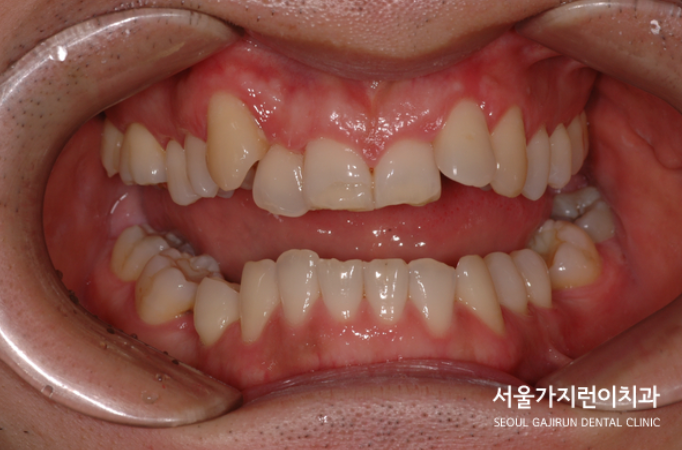

안녕하세요? 서울 가지런이치과 교정과 의원입니다. 오늘은 전치부의 교차 교합과 주걱턱 증상을 동반한 환자의 치아교정 사례를 가져와봤습니다.

상악 전치부가 심하게 내려앉고 하악 전치는 심하게 올라간 상태인것을 확인해볼 수 있는데요. 이가 맞물리지 못해 상하악 전치가 심하게 정출된 것을 볼 수 있었습니다.